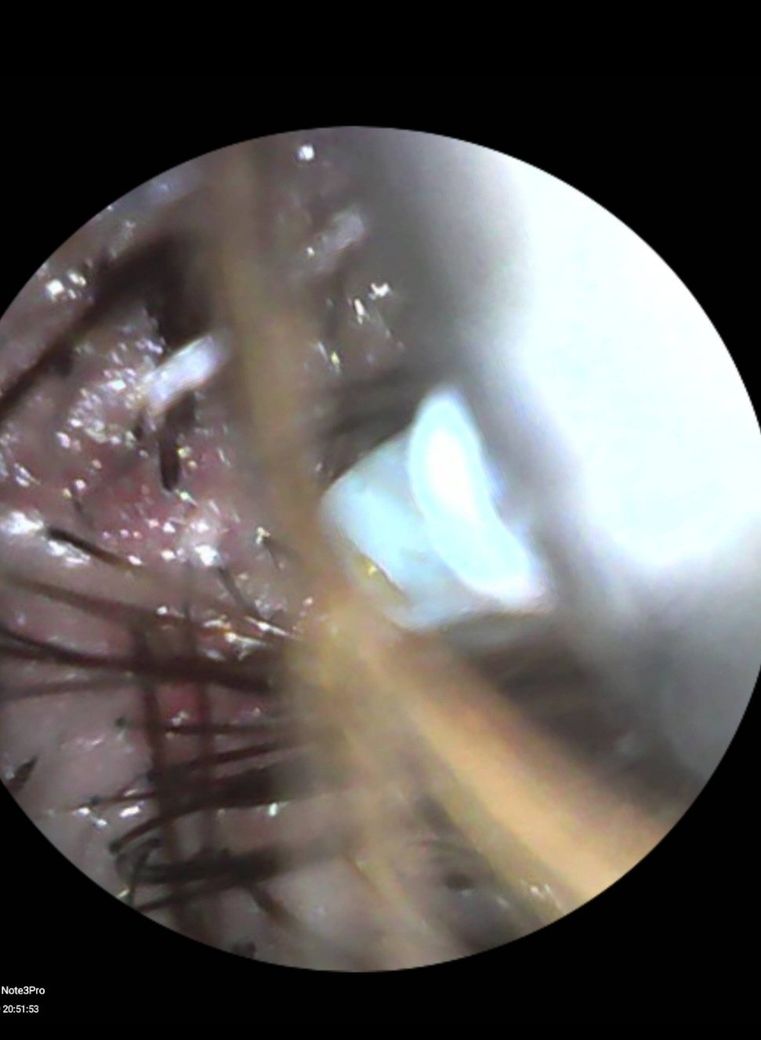

문제 부분을 귀 내시경이 있어서 두피 상태를 확인해보니 두피 여기저기가 붉게 변했고, 노란색 딱지가 덕지덕지 붙어 있는게 확인되었습니다.

사진보면 조명 문제일수 있지만 하얀색은 대부분 새치머리입니다.